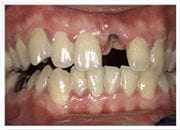

治療後